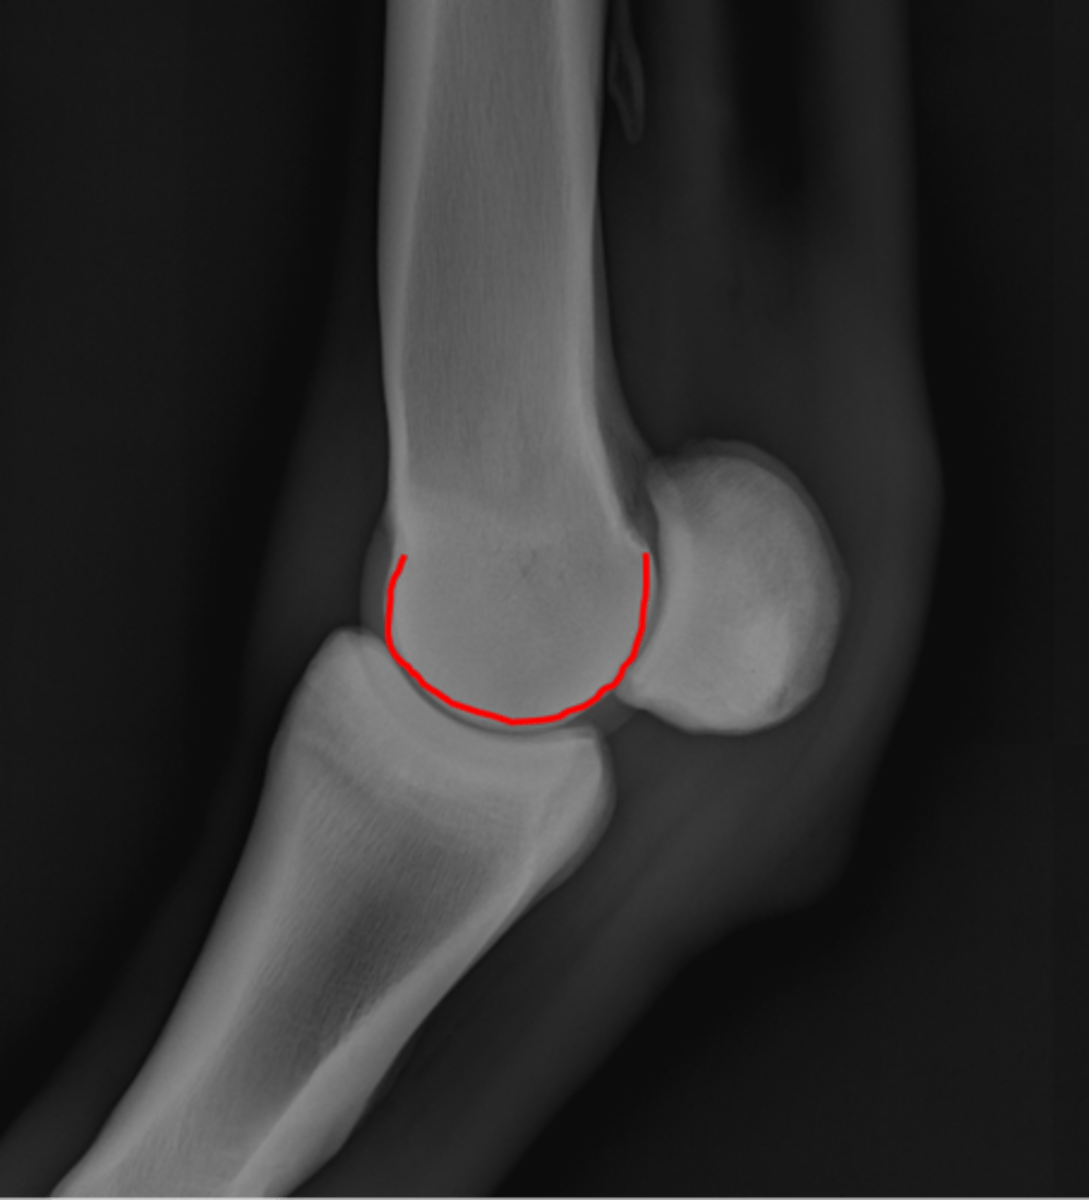

Fetlock joint, LM

ID joint and view

Fetlock joint, flexed LM

ID joint and view

Proximal sesamoid bone

Sagittal ridge

Condyles of third metacarpal bone

Palmar process of P2

Proximal sesamoid bones

Sagittal ridge

Attachment of collateral ligaments

Proximal sesamoid bones

Palmar process of P1

Condyles of the third metacarpal bone